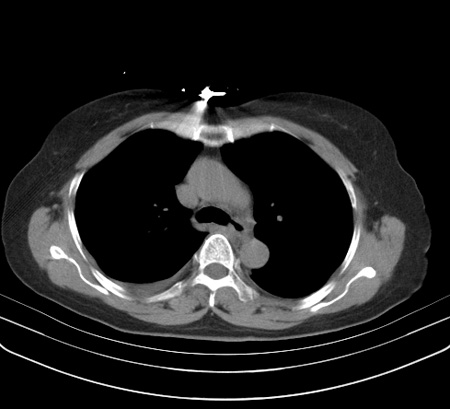

以下是引用余辉在2009-2-19 20:10:00的发言:[br]多考虑急性感染性病变,右中叶尚可见多枚小斑片状影,多为化脓性肺炎,双侧胸腔积液

以下是引用随光逐影在2009-2-19 20:33:00的发言:[br]1)考虑右肺炎症;建议抗炎治疗后复查。2)双侧胸腔积液(以右侧为甚)。

以下是引用花凤凰在2009-2-19 20:46:00的发言:[br]病人有发热,胸痛急性起病,主要病变位于右肺中叶外侧段,呈楔行改变,位于外带胸膜下,考虑为肺梗塞可能!!!!!!!!!!!!!!!!!!!!!!!!!!!!!!!!!!!